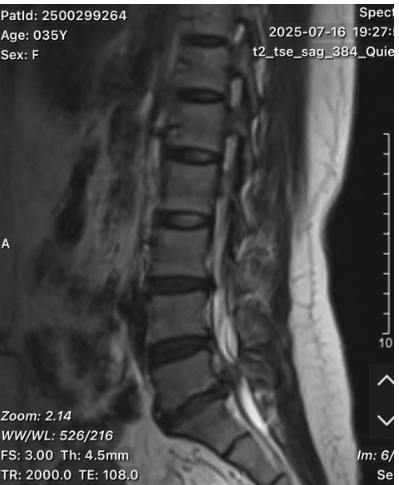

Kết quả chụp cộng hưởng từ (MRI) cột sống thắt lưng cho thấy bệnh nhân bị thoát vị đĩa đệm L5-S1 thể di trú - một thể nặng, với khối thoát vị lệch ra sau và sang phải, gây chèn ép nghiêm trọng lên rễ thần kinh. Đây chính là nguyên nhân dẫn đến đau kéo dài, rối loạn cảm giác và suy giảm vận động.

Kết quả chụp cộng hưởng từ (MRI) cột sống thắt lưng cho thấy bệnh nhân bị thoát vị đĩa đệm L5-S1 thể di trú. Ảnh: BVCC.